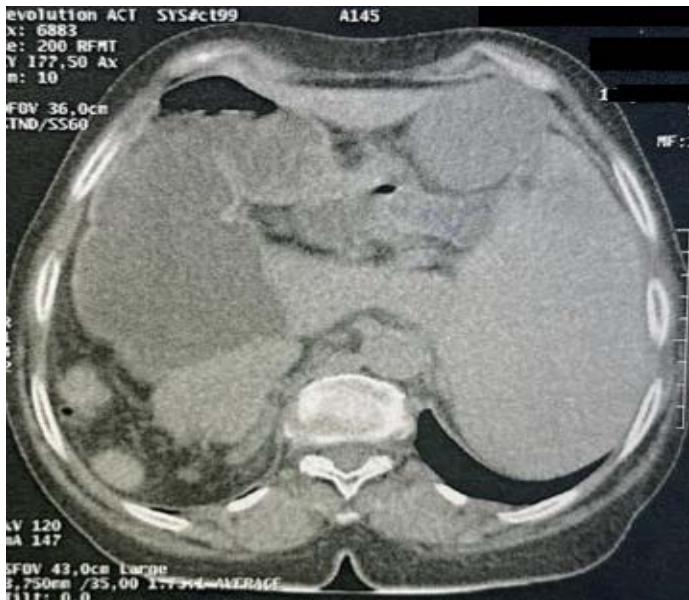

Situs inversus totalis is a rare congenital malformation that results in mirror positioning of the thoracic and abdominal organs. Situs inversus abdominalis is a right-left inversion limited to the abdomen; The association of situs inversus with intestinal band occlusion is infrequent; We report a case of acute intestinal obstruction associated with situs inversus abdominalis, the diagnosis was confirmed by abdominopelvic CT scan, and the treatment consisted of a gallbladder resection with anastomosis, with good postoperative results.

Intrusive intestinal obstruction diagnosis in abdomen.